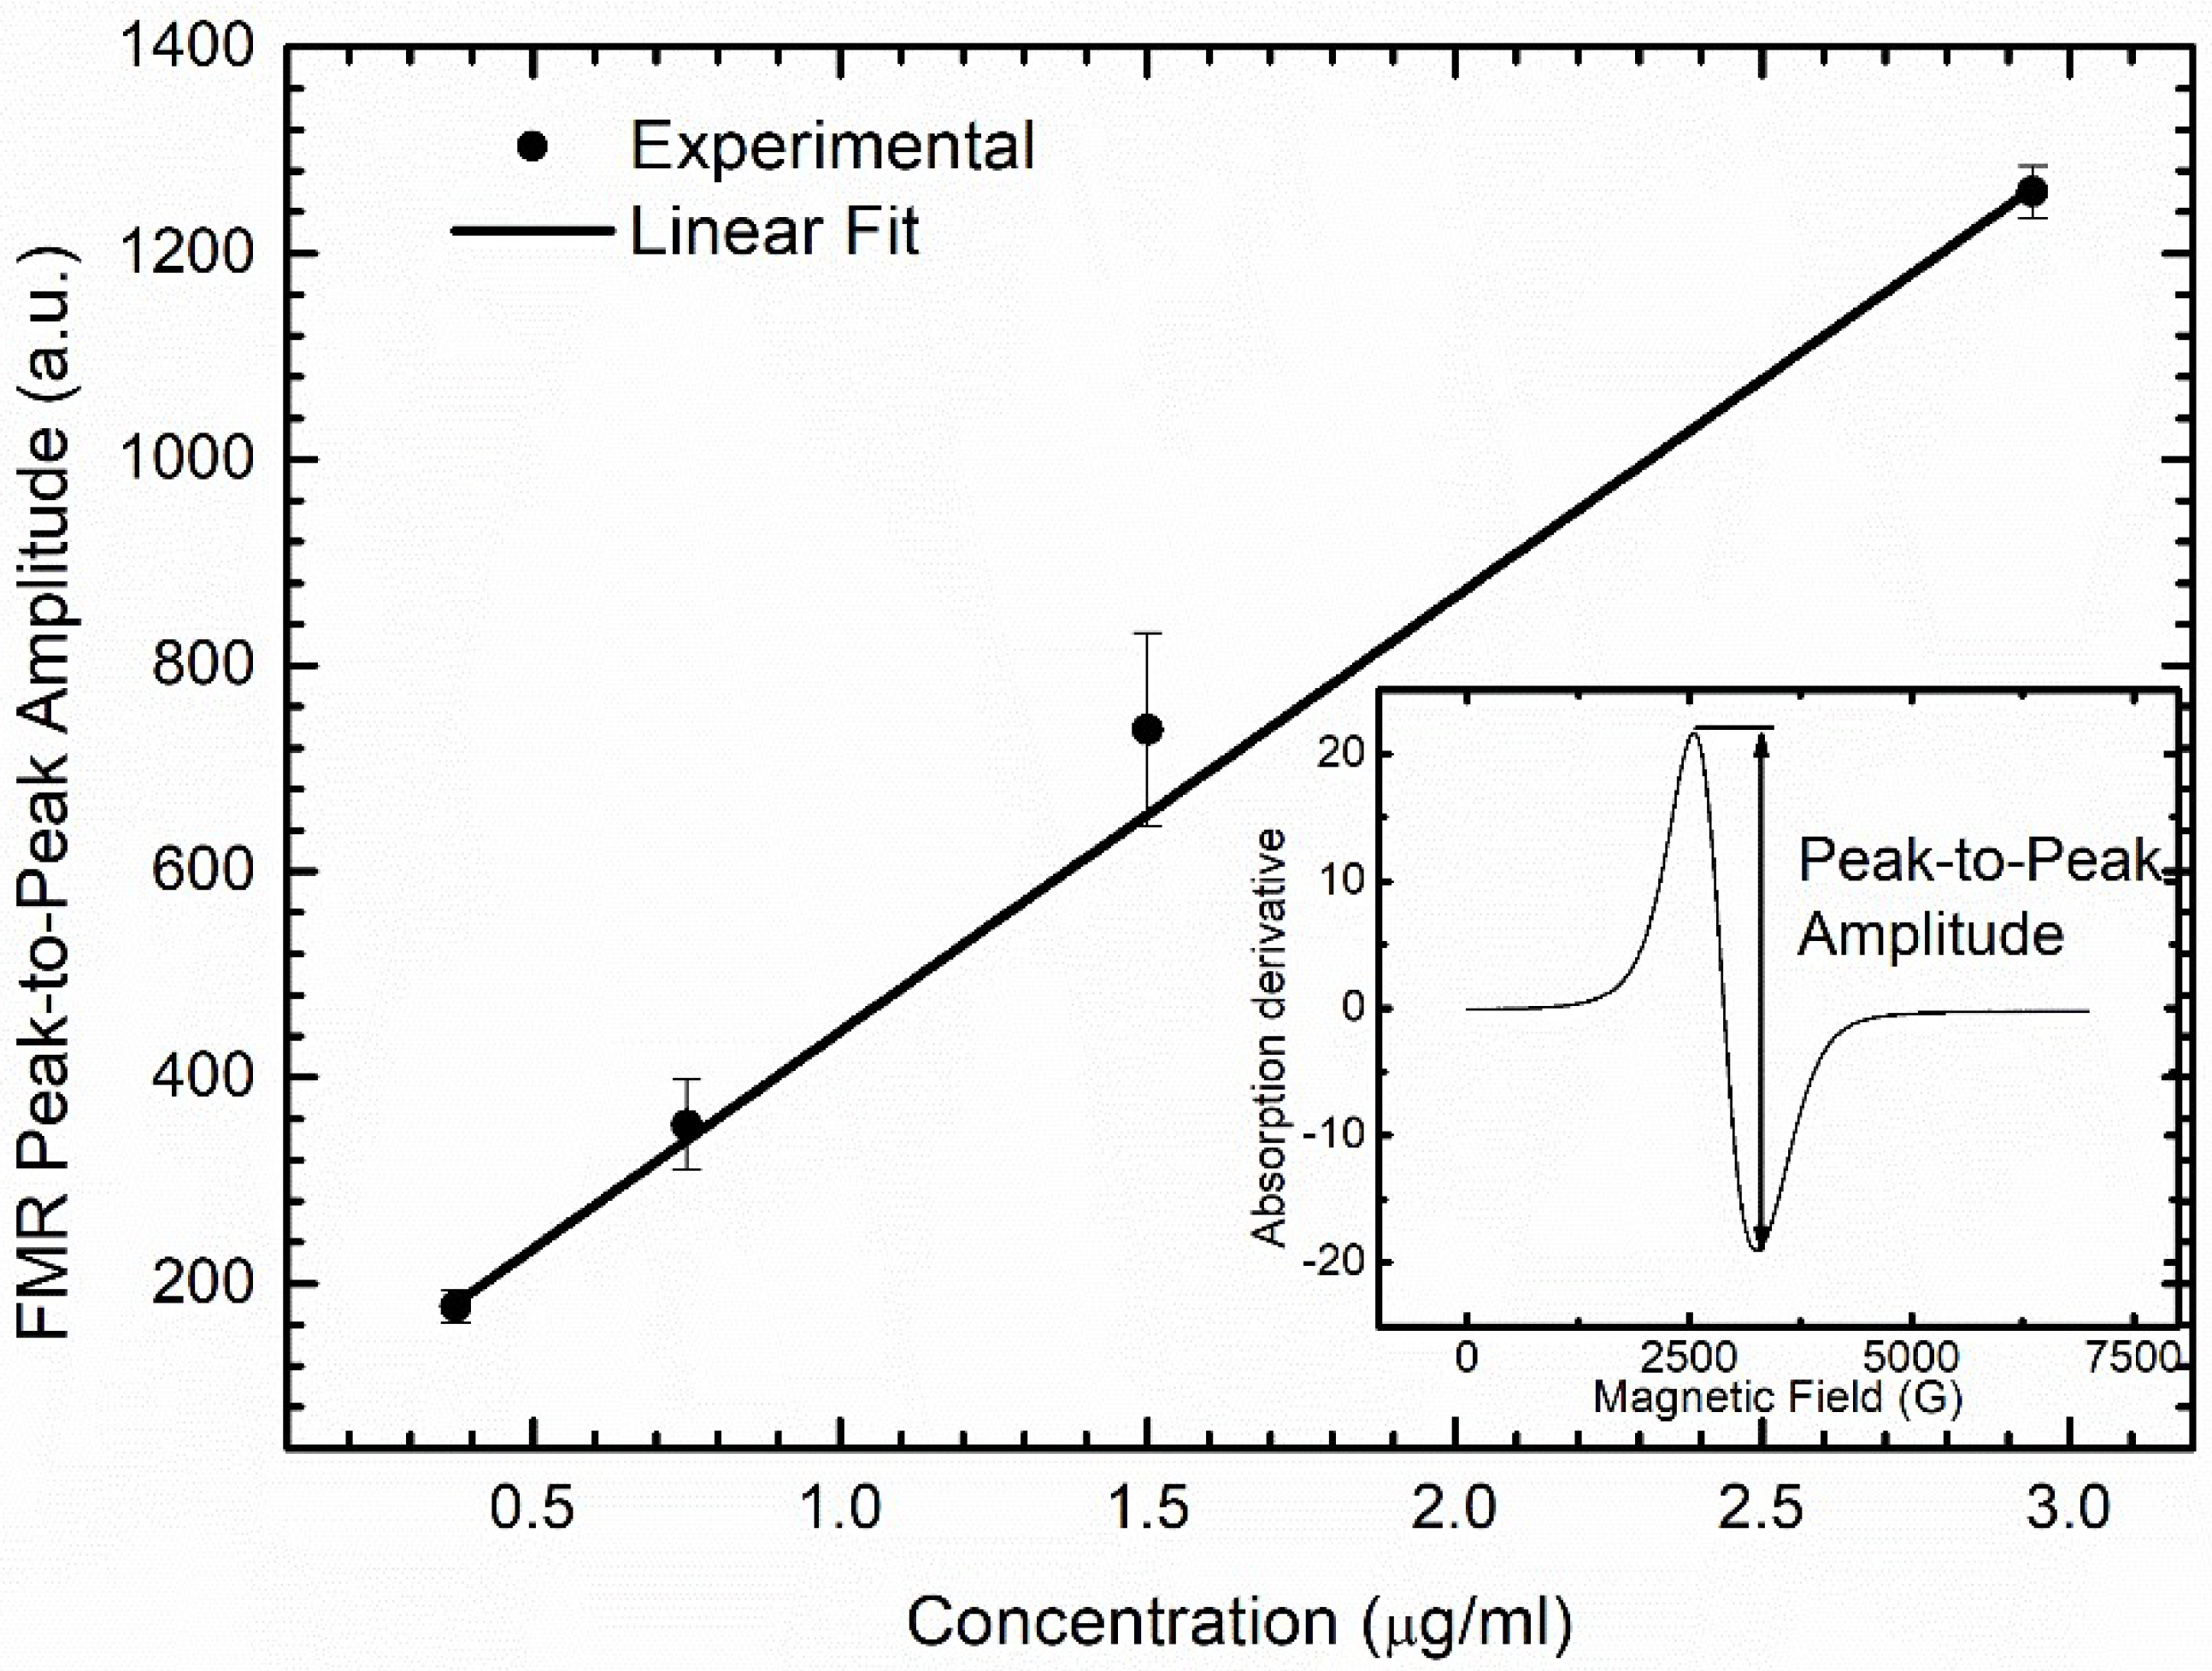

2.6. DMSA-MNP Detection and Quantification in Organs by Ferromagnetic Resonance (FMR)

3.5. DMSA-MNP Detection in the Organs